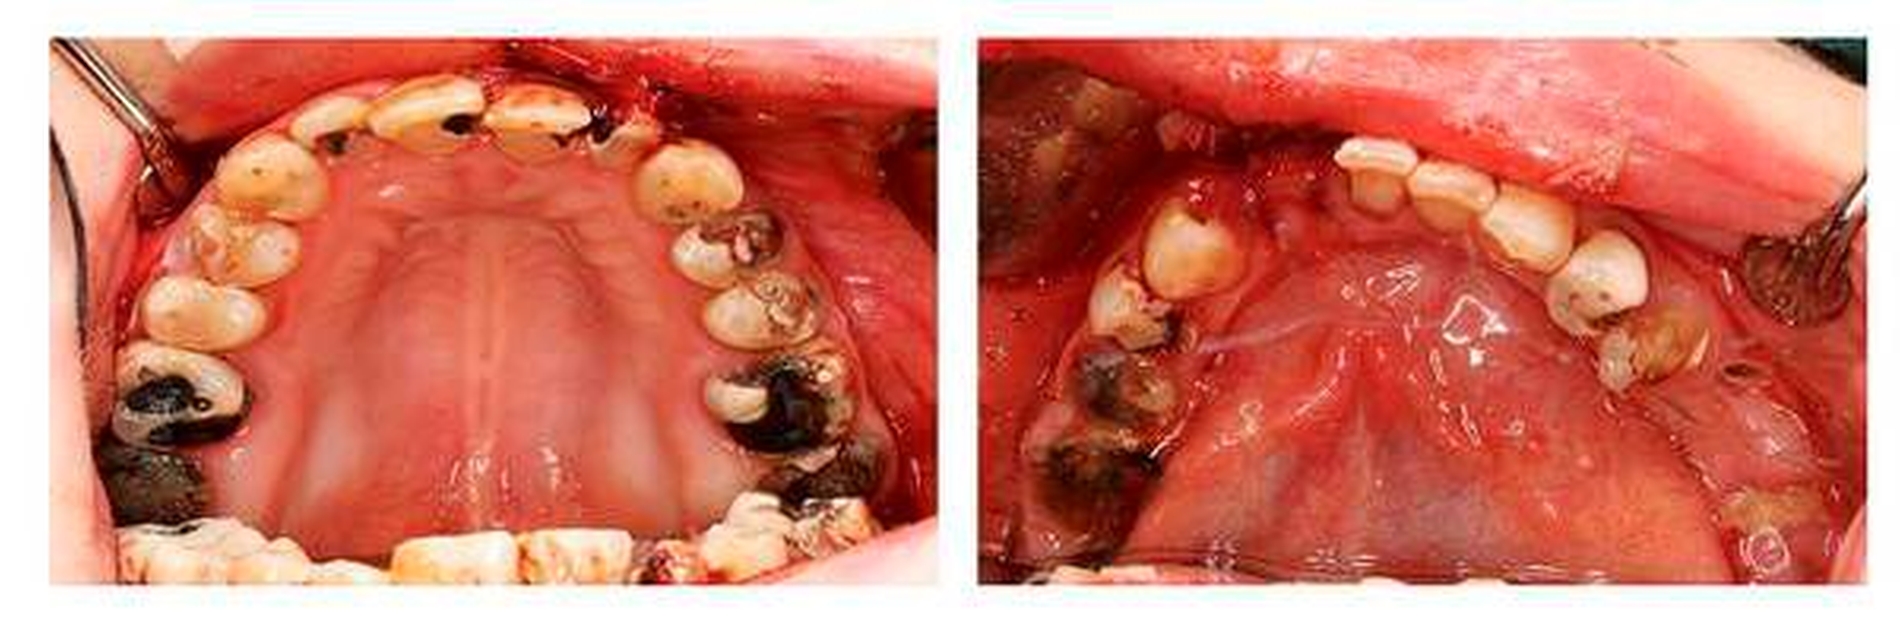

Die Patientin war stark desorientiert und agitiert. Die Fremdanamnese war bis auf einen langjährigen Crystal-Meth-Abusus, der polizeilich bestätigt wurde, unauffällig. In der CT-Kopf/Hals-Untersuchung konnten intrazerebrale Verletzungen ausgeschlossen, der zusätzliche klinische Verdacht einer Nasenbeinfraktur konnte bestätigt werden. Die weitere klinische Inspektion ergab intraoral den Befund eines kariös tief zerstörten Restzahngebisses mit multiplen, teils gelockerten, nicht erhaltungswürdigen Zähnen.

Eine weitere Nebenwirkung ist der sogenannte Meth Mouth, der sich klinisch unter anderem durch eine Xerostomie sowie ausgeprägte kariöse Läsionen manifestiert. Zusätzlich gibt es erste Hinweise auf einen möglichen pathophysiologischen Zusammenhang zwischen einem langjährigen Konsum von Crystal Meth und der Entwicklung von oralen Knochennekrosen, die in ihrem klinischen Erscheinungsbild der Antiresorptiva- beziehungsweise der Medikamenten-assoziierten Osteonekrose der Kiefer (MR-ONJ) ähneln.

Neben dem extrem hohen Abhängigkeitspotenzial sowie einer Vielzahl an internistischen, neurologischen und psychiatrischen Nebenwirkungen wird als relevante Nebenwirkung im oralen und dentalen Bereich über den „Meth Mouth“ berichtet, der durch Xerostomie, ausgeprägte kariöse Läsionen, Schmelzerosionen, Knirschen und Bruxismus, Muskeltrismus und Kieferklemmen beziehungsweise Kiefersperren gekennzeichnet ist [De-Carolis et al., 2015; Rommel et al., 2015; 2016a,b].